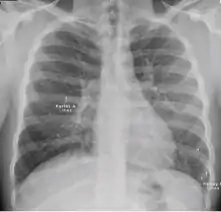

Chest x-ray showing coarse reticulonodular densities on the lower right lung of post-primary pulmonary TB.

2. Any cavitary lesion - Lucency (darkened area) within the lung parenchyma, with or without irregular margins that might be surrounded by an area of airspace consolidation or infiltrates, or by nodular or fibrotic (reticular) densities, or both. The walls surrounding the lucent area can be thick or thin. Calcification can exist around a cavity.

3. Nodule with poorly defined margins - Round density within the lung parenchyma, also called a tuberculoma. Nodules included in this category are those with margins that are indistinct or poorly defined (tree-in-bud sign[3]). The surrounding haziness can be either subtle or readily apparent and suggests coexisting airspace consolidation.

Chest x-ray showing nodule with margins that are indistinct or poorly defined (tree-in-bud sign) in post-primary pulmonary TB.